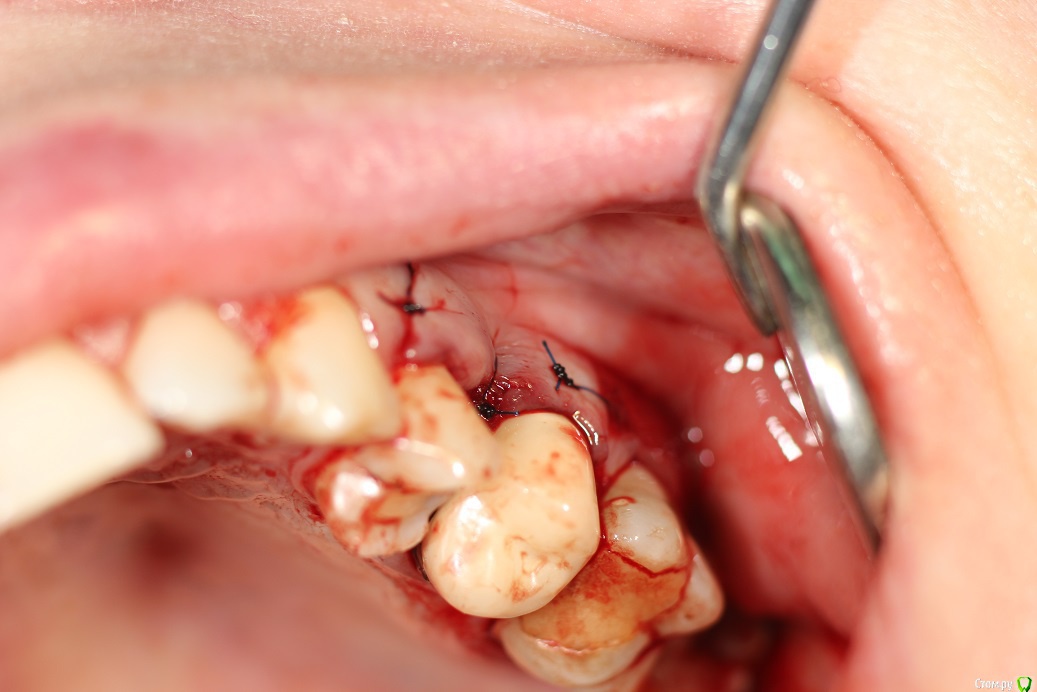

Марья Моревна Опубликовано 24 февраля, 2020 Поделиться Опубликовано 24 февраля, 2020 Смею предположить,что у доктора не будет под рукой прф.Тогда после аккуратного извлечения секвестра и нежного легкого кюретажа поставьте губку стимул-осс по инструкции.На сосочки шов монофиламент нерезорбируемой 6.0 или 5.0 ,если можно,под увеличением.Сближать,но не стягивать.Ибупрофен по 400 - 2р.в день 3 дня,по 1р.в день еще 3 дня.Солкосорил на швы наносить. Хлоргексидин пассивно ванночки.Такая конкретика устраивает? Это все Вам может дать заживление десны.Но не в этом основная проблема.Надо разобраться с хроникой около пятого и с потерей объема кости в вестибуло-оральном направлении.Для этого и нужно КТ.Какие препараты она принимает,тоже интересно. Ссылка на комментарий

kuziy12 Опубликовано 8 марта, 2020 Автор Поделиться Опубликовано 8 марта, 2020 Как то так. Попытался вообще без откидывания, но тогда бы секвестр десну порвал, большой слишком. Уже его чуть сдвинул:Убрал грануляции:Ушился:Это секвестр: 3 Ссылка на комментарий

Марья Моревна Опубликовано 8 марта, 2020 Поделиться Опубликовано 8 марта, 2020 Разрез лучше делать не прям по центру сосочка,а немного ближе к зениту зуба,где-то на 1/3.Оптрагейтом не пользуетесь? Ссылка на комментарий

kuziy12 Опубликовано 9 марта, 2020 Автор Поделиться Опубликовано 9 марта, 2020 Разрез лучше делать не прям по центру сосочка,а немного ближе к зениту зуба,где-то на 1/3.Оптрагейтом не пользуетесь?есть, здесь не стал ставить. Наоборот учили по сосочку делать, чтобы рецессии не было Ссылка на комментарий